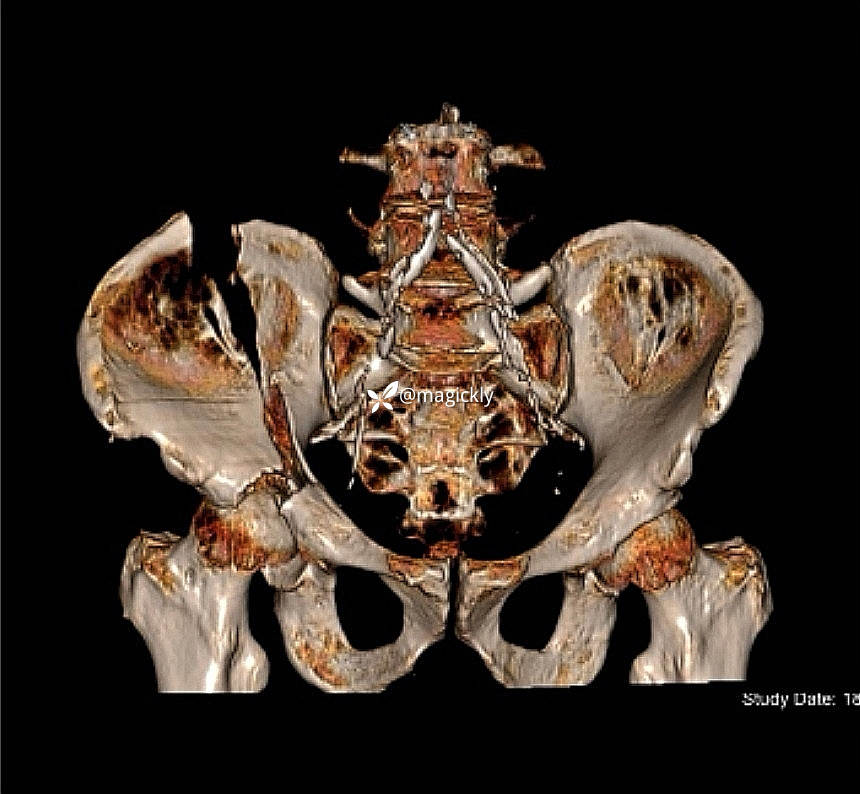

【治疗经过及结果】

img